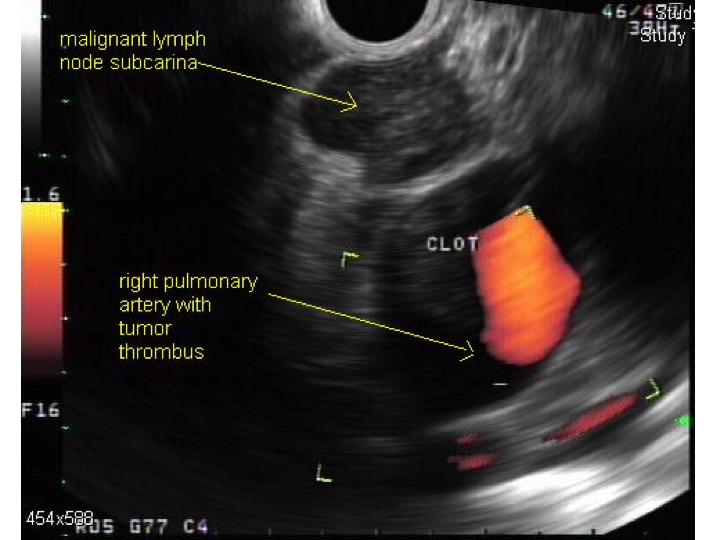

(A) Endobronchial tumor visible in an airway. (B) Ultrasound image of a

(A) Endobronchial tumor visible in an airway. (B) Ultrasound image of a Endoscopic Biopsy Of Lung Mass Quizlet Endoscopic removal of lung tissue via the chest wall, which may also be referred to as. A lung biopsy is a medical procedure where a doctor takes a tissue sample from the lungs to examine it under a microscope. A lung biopsy is a procedure that removes a sample of lung tissue or cells to determine if there is a. Endoscopic Biopsy Of Lung Mass Quizlet.